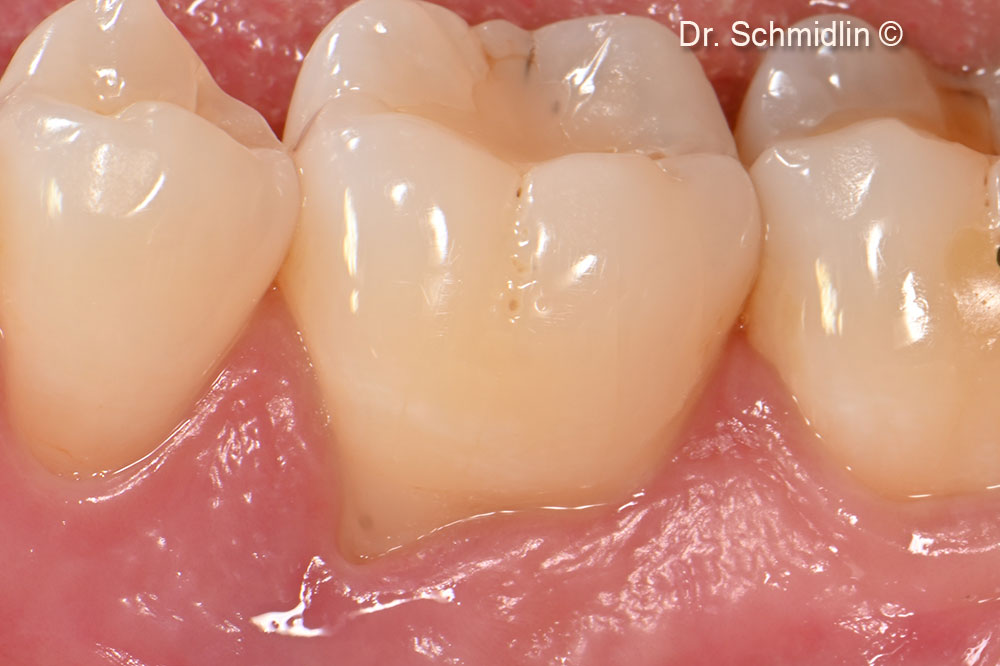

Preoperative clinical view of the affected site